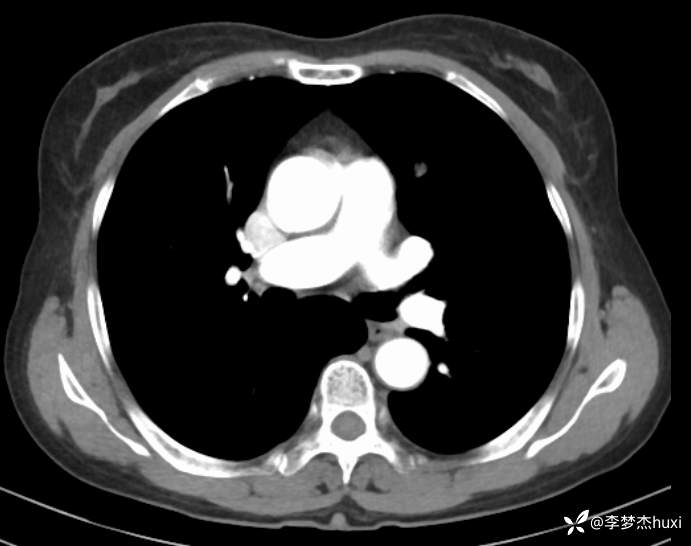

1.现病史:患者老年 女,患者于入院前3天(2024-06-02)体检查胸部CT:左肺部分实性结节,右肺磨玻璃结节,左肺上叶实性结节--性质?建议肺结节门诊会诊检查;双肺索条,双肺下叶条絮状高密度影--考虑肺血坠积效应,主动脉壁钙化,双侧胸膜局部增厚,左侧乳腺钙化点。2024-06-04查胸部增强CT:左肺上叶实性结节--占位?建议结合病理;左肺部分实性结节,右肺磨玻璃结节,建议肺结节门诊会诊检查;双肺索条,主动脉壁钙化,双侧胸膜局部增厚,左侧乳腺钙化点。患者目前无咳嗽、咳痰,无发热,无胸痛,今为求进一步诊治来我院,门诊以“肺诊断性影像异常”收入院。

4.辅助检查:2024-06-02查胸部CT:左肺部分实性结节,右肺磨玻璃结节,左肺上叶实性结节--性质?建议肺结节门诊会诊检查;双肺索条,双肺下叶条絮状高密度影--考虑肺血坠积效应,主动脉壁钙化,双侧胸膜局部增厚,左侧乳腺钙化点。2024-06-04查胸部增强CT:左肺上叶实性结节--占位?建议结合病理;左肺部分实性结节,右肺磨玻璃结节,建议肺结节门诊会诊检查;双肺索条,主动脉壁钙化,双侧胸膜局部增厚,左侧乳腺钙化点。。